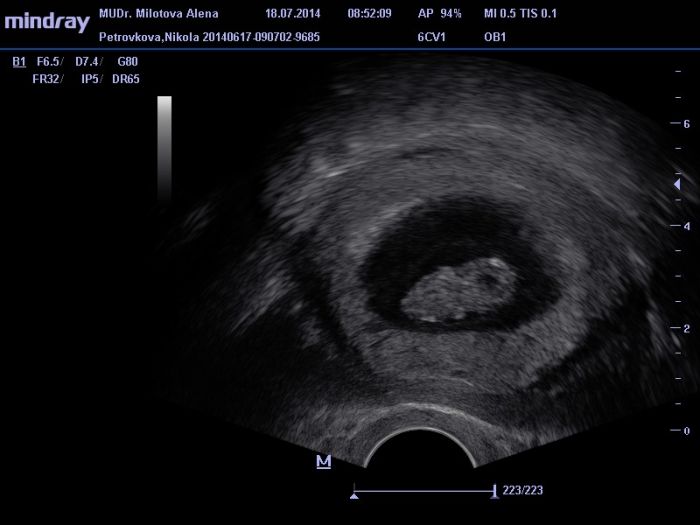

Ahojky holky tak mam po ko a vse v poradku akorad mi broucka nezmerila :( sakra ... Dalsi ko a rovnou zapis a odbery a moc 28.7. :) Mam radost ze pindik malej roste pupiiik :-* posilam i par fotecek :)

tak ted nevim jestli ty fotky vy uvidite :) takze jeste jednou :)